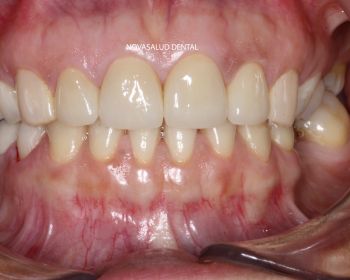

Tratamiento: coronas ceramo-metal unitarias en frente anterior.

Paciente acude a consulta con 4 coronas en sector anterior recién colocadas en otra clínica dental. La paciente no esta nada contenta con el resultado estético. Nos pide que le cambiemos las coronas. Decidimos retirar las 4 piezas ferulizadas y realizar 4 coronas unitarias, es decir, separadas individualmente para ganar en estética. El paciente mejora la estética dental con el tratamiento.